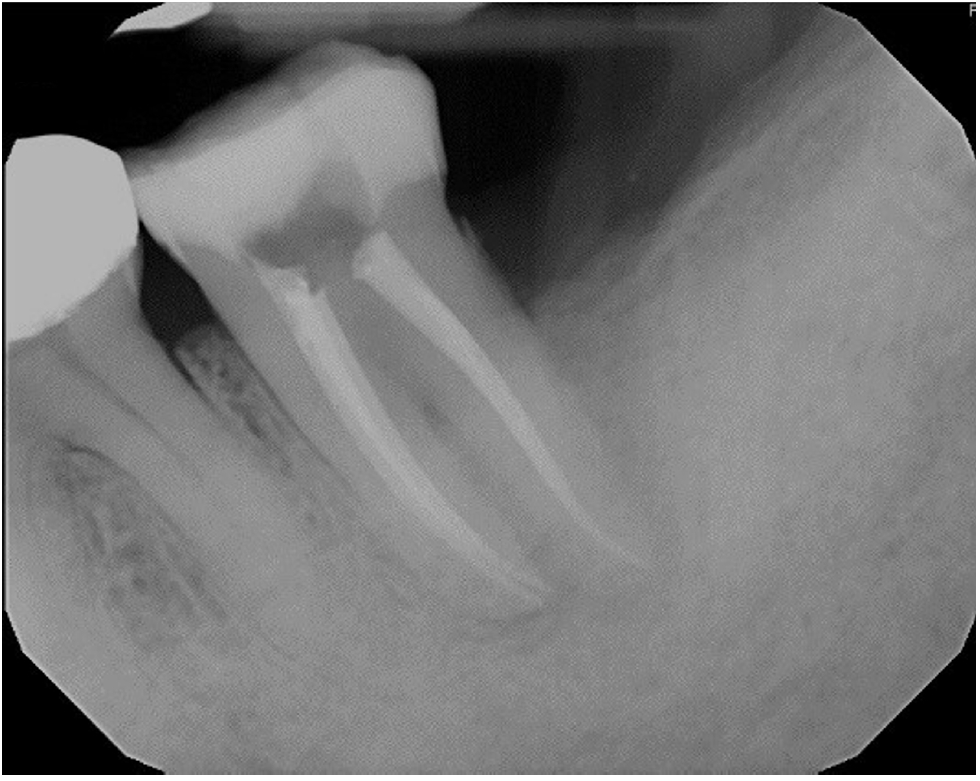

Working lengths were determined using an electronic apex locator (RootZX; J Morita, Kyoto, Japan) and confirmed with a periapical radiograph, which also showed a radiopaque fragment consistent with a cemental tear (Figure 2). The chamber was flooded with 5% sodium hypochlorite, and the canals were instrumented using size 8, 10, 15, and 20 K files, followed by a 25/.07 Primary Wave One Gold (Dentsply Sirona, Charlotte, NC, USA) reciprocating file. Irrigation was performed with 12 mL of 5% sodium hypochlorite with ultrasonic activation for 30 seconds per canal. Calcium hydroxide was placed as an intracanal medicament with a lentulo spiral, and the tooth was temporized with a sterile sponge and Cavit (3M ESPE, St. Paul, MN, USA). The patient was informed to return in 2 weeks for completion of the root canal.

Figure 2.

Working length radiograph showing radiopaque fragment consistent with a cemental tear along distal root (red arrow).

Figure 2. Working length radiograph showing radiopaque fragment consistent with a cemental tear along distal root (red arrow).